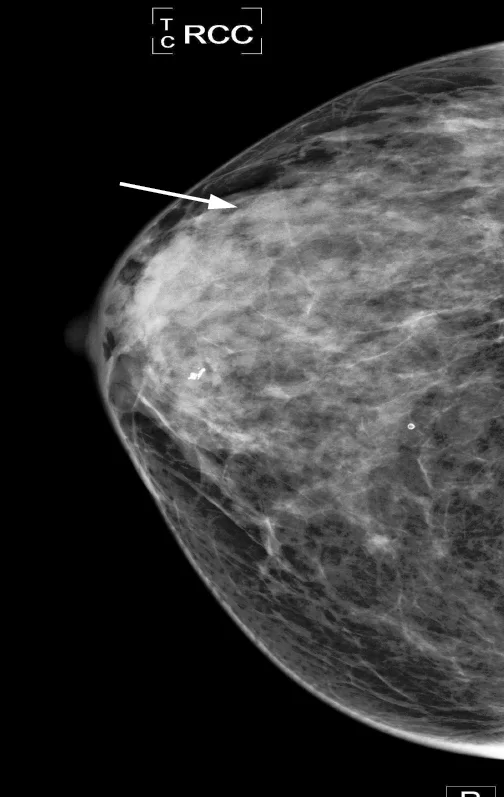

This is a cancer.

This mammogram was taken here at the clinic. The woman who had this mammogram was in her 50s and has a small (stage 1) breast cancer.  This client didn't have any symptoms. She came to see us for screening.

I knew that this finding was a cancer the moment I saw it. Notice the white spot surrounded by the star-like pattern.  The star-like pattern is called architectural distortion and is highly suggestive of cancer. Notice also the position of the finding. It is located behind the lighter tissue of the breast.  This is called an asymmetry, another highly suspicious finding.

No additional testing here was needed. This client went straight to biopsy, where this finding was found to be malignant.